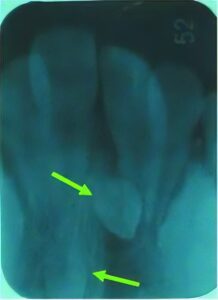

萌出障害

何らかの原因で歯が生えてこないことがあります。レントゲン写真等での検査や何らかの治療が必要なこともあります。